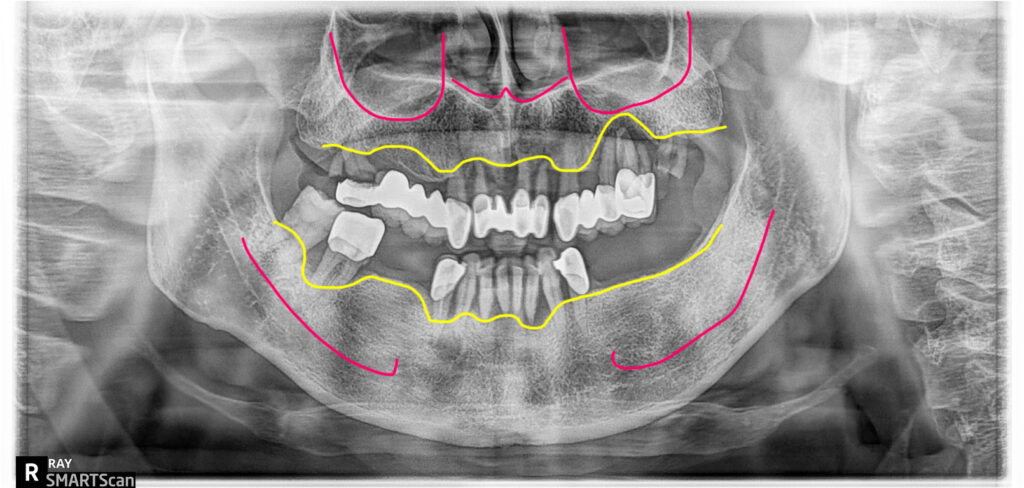

잇몸질환(치주염)이 심한 전체임플란트 사례의

치료전 엑스레이

전체임플란트 치료전후

파노라마 비교

치료전 파노라마 상에서 심하게 치조골이 파괴된 자리인 왼쪽 위 작은어금니 부분은 임플란트를 심지 않고 연결하는 방식으로 처리했구요. 위쪽 어금니부분에는 간단한 상악동 이식술을 시행했습니다. 아래 오른쪽 송곳니부분에도 뻐이식이 진행되었어요. 이렇게 발치와 임플란트식립, 뼈이식이 모두 하루에 진행이 됩니다. 저는(이한나원장) 수천명의 전체임플란트 치료 사례를 시술했으며, 손이 빠르고 정확해서 수술시간이 빠릅니다. 수술시간이 빠르면 경과도 좋고 환자도 덜 힘듭니다.